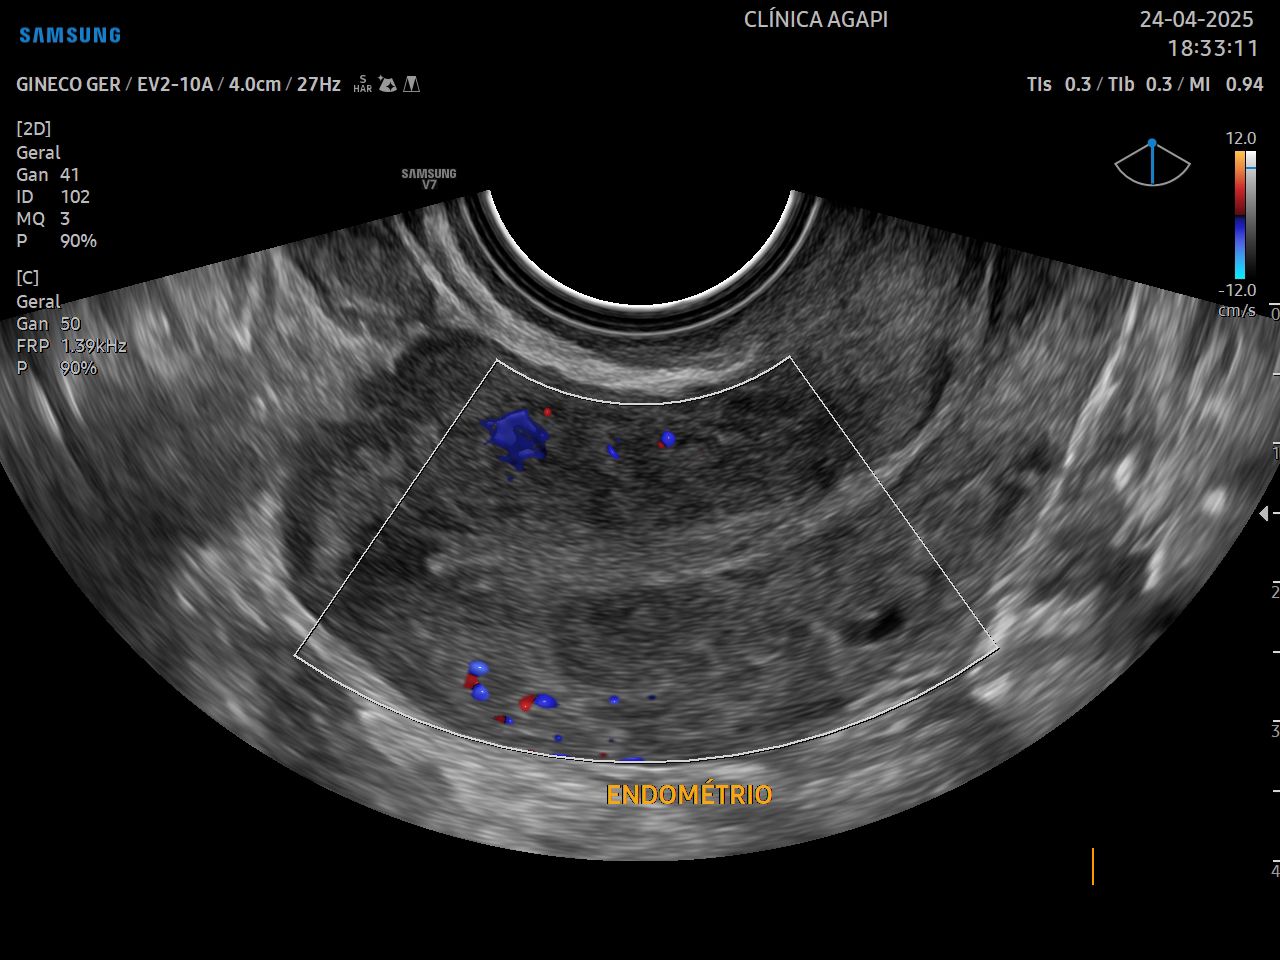

Avalia o útero e os ovários, assim como a presença de outras estruturas como massas, cistos e tumores pélvicos. Indicado para mulheres que já iniciaram a vida sexual, sendo realizado via transvaginal.

Pode ser realizado de rotina ou para avaliação de sintomas específicos.